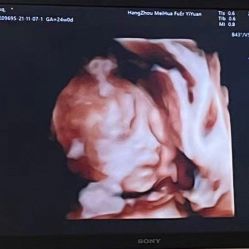

• -杭州贝瑞斯美华妇儿医院·早孕·产检·儿科

相册

米老鼠 上传于 21-11-08 | 报错